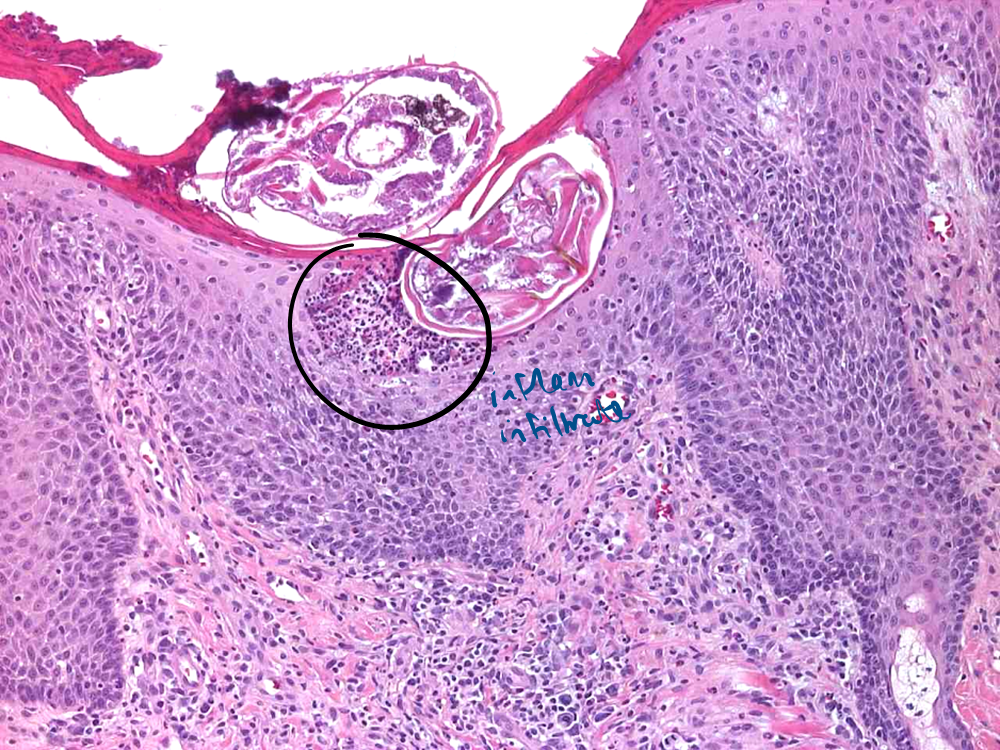

How does demodectic mange present histologically?

Intrafollicular mites with characteristic cigar shape

Perifollicular mixed dermatitis

Possible furuncolusis

Abscess formation due to bacterial breech